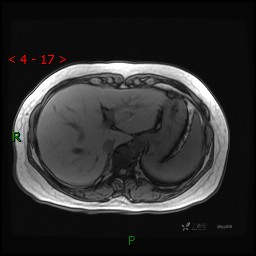

动态增强(动脉早期、动脉晚期、门脉期)